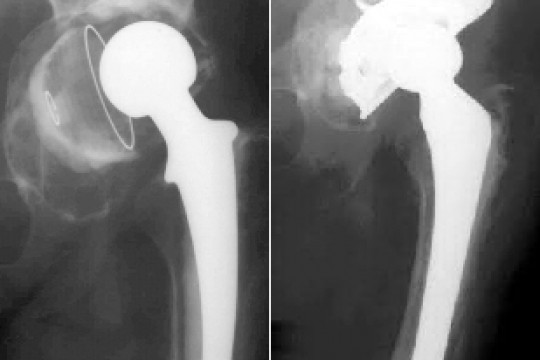

A szövetbank megkönnyítené a csontpótlást

2015-01-14 14:49:06 // Bodolai Gyöngyi

A Marosvásárhelyen létesítendő sejt- és szövetbank kapcsán évek óta folyik az ígérgetés, amelyek sze...